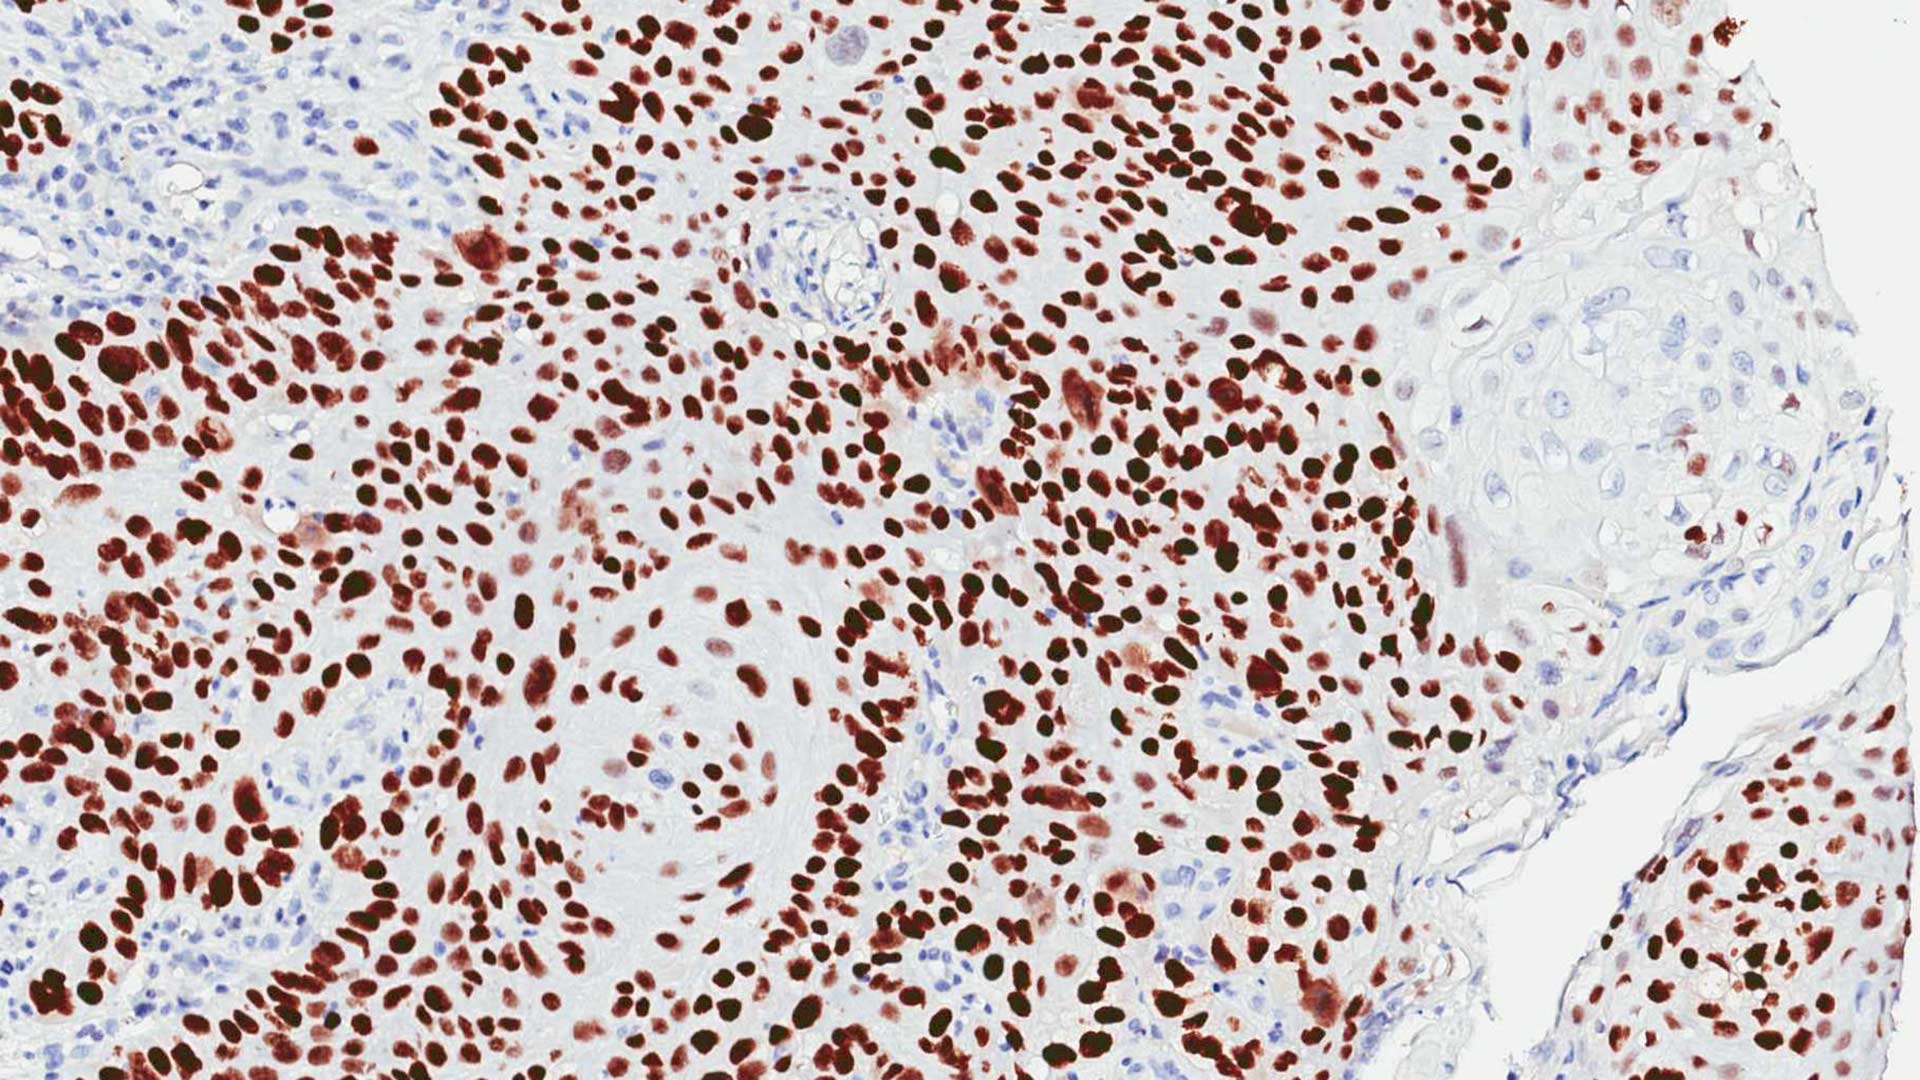

Mills’ team identified a cascade of four proteins that act like a series of dominos to activate ∆Np63α. Some of these proteins were already known to be involved in promoting other kinds of cancer, so there were already drugs in clinical trials to deactivate them.

When the Mills group added these drugs to patient-derived cancer stem cells growing in a Petri dish, the cells became less aggressive, less mobile, and slower growing. Mice with these cancerous squamous cells treated with these drugs developed smaller tumors.